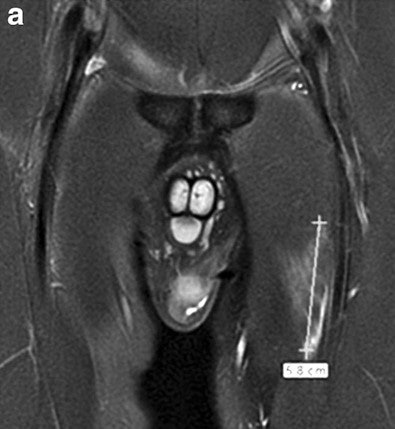

Serner, Roemer, and colleagues developed a detailed multidimensional MRI assessment approach for acute groin injuries that focuses on musculotendinous injuries, including location, grading, and lesion extent, as well as other nonacute findings, and determines intra- and interrater reproducibility of such assessments.

The protocol the researchers developed assessed grade, location, and extent of muscle strains; perilesional hematoma; and other nonacute findings commonly associated with groin pain, such as location and extent of edema.

Musculotendinous lesions were graded identically for acute and nonacute lesions on a scale from 0 to 3, with 0 being no imaging abnormality and 3 being complete musculotendinous disruption/tear or avulsion from the tendinous attachment.

In the 75 athletes, the researchers scored 85 different acute muscular lesions. One radiologist found 18 athletes were MRI-negative for acute lesion injuries, and the other radiologist found 17 athletes were MRI-negative for acute lesion injuries. The most commonly affected muscle was the adductor longus (42.7%), followed by the rectus femoris (16.3%).